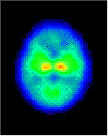

Click on image above to view full-size image.

The high CMRGlc during 3 to 10 years corresponds to the period of exuberant connectivity in humans and is probably required to meet the energy demands of the neuronal processes and synapses that are also in excess by about a factor of two compared to adults. Shown above are PET scans from 3 different ages showing the relative glucose metabolic rate. Beneath the PET scans are drawings showing the relative complexity of the dendritic structure of cortical neurons. The progressive increase in glucose utilization seen in development is consistent with anatomical studies showing an expansion of dendritic fields (and synaptic connectivity) and an increase in capillary density in the human frontal cortex during the same period. Thus, it is possible that the decrease in glucose metabolic rate in the adult reflects a "pruning" of excessive neuronal connectivity and a selective stabilization of the remaining neuronal connections.